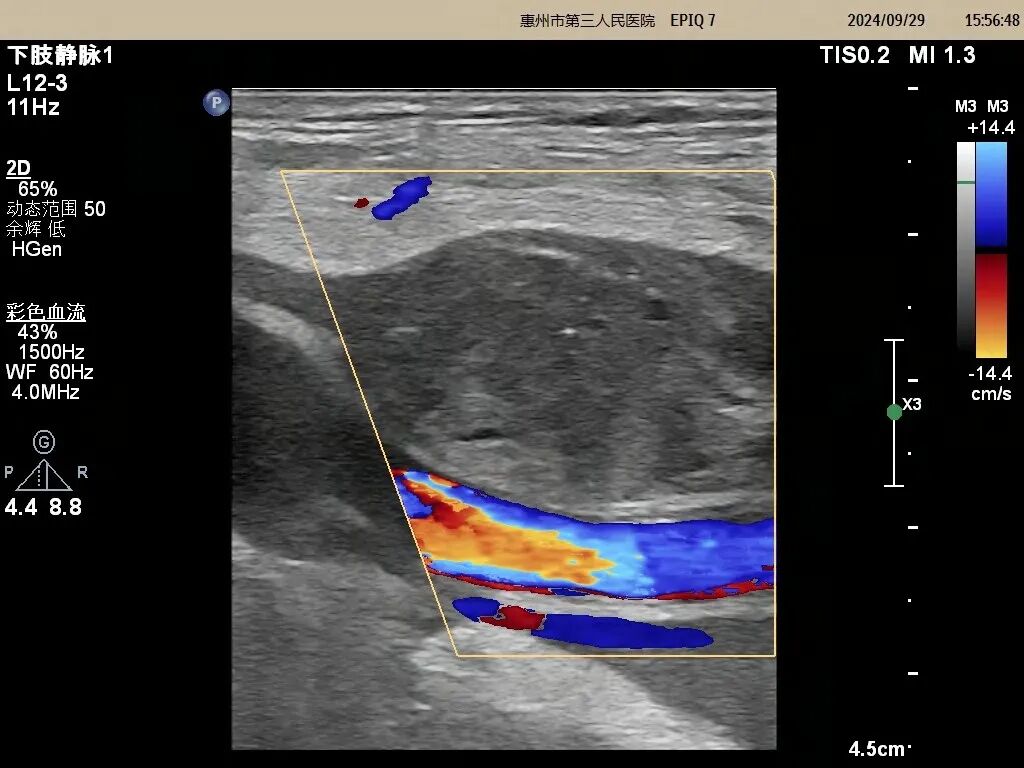

(術后圖片)